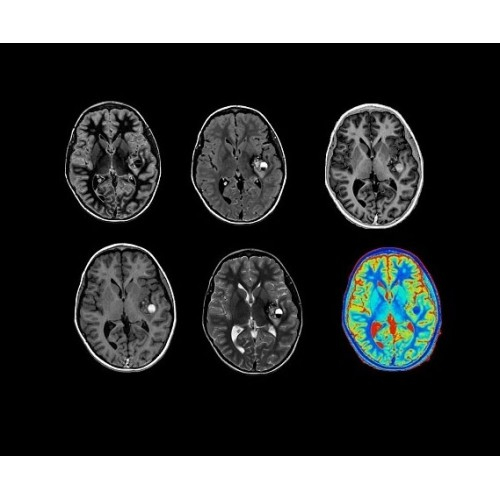

SIGNA PET/MR 3.0T — это гибридная система, в которой совмещаются две принципиально разные технологии — магнитно-резонансную томографию (МРТ) и позитронно-эмиссионную томографию (ПЭТ). Система отличающийся высокой чувствительностью и эффективностью и предназначена для диагностики в области онкологии, неврологии, кардио-васкулярных исследований, исследований воспалительных процессов.

Компания GE Healthcare представляет революционную, полностью интегрированную систему SIGNA PET/MR1, в которой сочетаются времяпролетная технология (TOF) и возможности напряженности магнитного поля 3.0 Тл. Мы поможем вам поднять исследования на более высокий уровень. SIGNA PET/MR позволяет достичь впечатляющей точности и скорости исследований, а благодаря новейшей технологии реконструкции Q.Clear2 качество изображений улучшается в два раза. Кроме того, в систему включен полный набор клинических приложений и гибких катушек для проведения любых видов исследования, открывая для вас возможности визуализации, о которых вы даже не догадывались.

Система SIGNA PET/MR предлагает впечатляющие клинические возможности и открывает доступ к наиболее полным пакетам программных приложений.

• Q.Clear — в основу технологии легли накопленные знания о том, как минимизировать помехи при реконструкции и получить четкое изображение. При значительном улучшении качества изображения сохраняется точность расчетов. Сочетание технологии TOF и реконструкции Q.Clear — ваш надежный помощник для получения точных и достоверных данных.

Стандартный пакет приложений SIGNA Works позволит вам достичь желаемых результатов в клинической практике благодаря набору высокоэффективных средств визуализации. Программные приложения, входящие в состав данных клинических пакетов, включают широкий спектр контрастов, функции обработки 2D- и 3D-данных, а также возможность коррекции артефактов движения. SIGNA Works предоставляет набор инструментов, необходимых для проведения эффективного клинического исследования.

• Специальный пакет приложений для измерения и сравнения объемных изображений ЦНС с нормами поможет вам в диагностике нейродегенеративных заболеваний, а дополнительные инструменты визуализации — в постановке точного диагноза с помощью бета-амилоидов и радиоизотопных маркеров ФДГ.